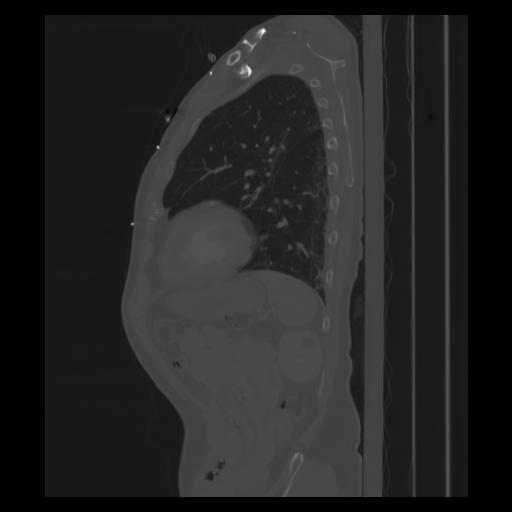

30 CUERPO,CE,Sagittal,3.000,CUERPO,Sagittal,